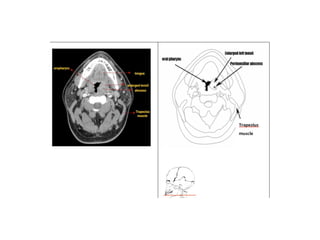

The relationship of airway obstruction

and dentofacial structures

• Airway obstruction, coupled with loss of

lingual and palatal pressure of the tongue,

produces alterations in the maxilla. The

positioning of the tongue also plays an

important role in mandibular development.

The tongue displaced downward can lead to a

retrognathic mandible; and an interposed

tongue can lead to anterior occlusal anomalies.

• maxillary changes can be viewed in the transverse

direction, producing a narrow face and palate often

linked with cross bite; in the anteroposterior direction,

producing maxillary retrusion; and in the vertical

direction causing an increase in palatal inclination as

related to the cranial base and excessive increases of

the lower anterior face height.

• The most commonly found occlusal alterations are

cross bite (posterior and/or anterior), open bite,

increased over jet, and retroclination of the maxillary

and mandibular incisors.